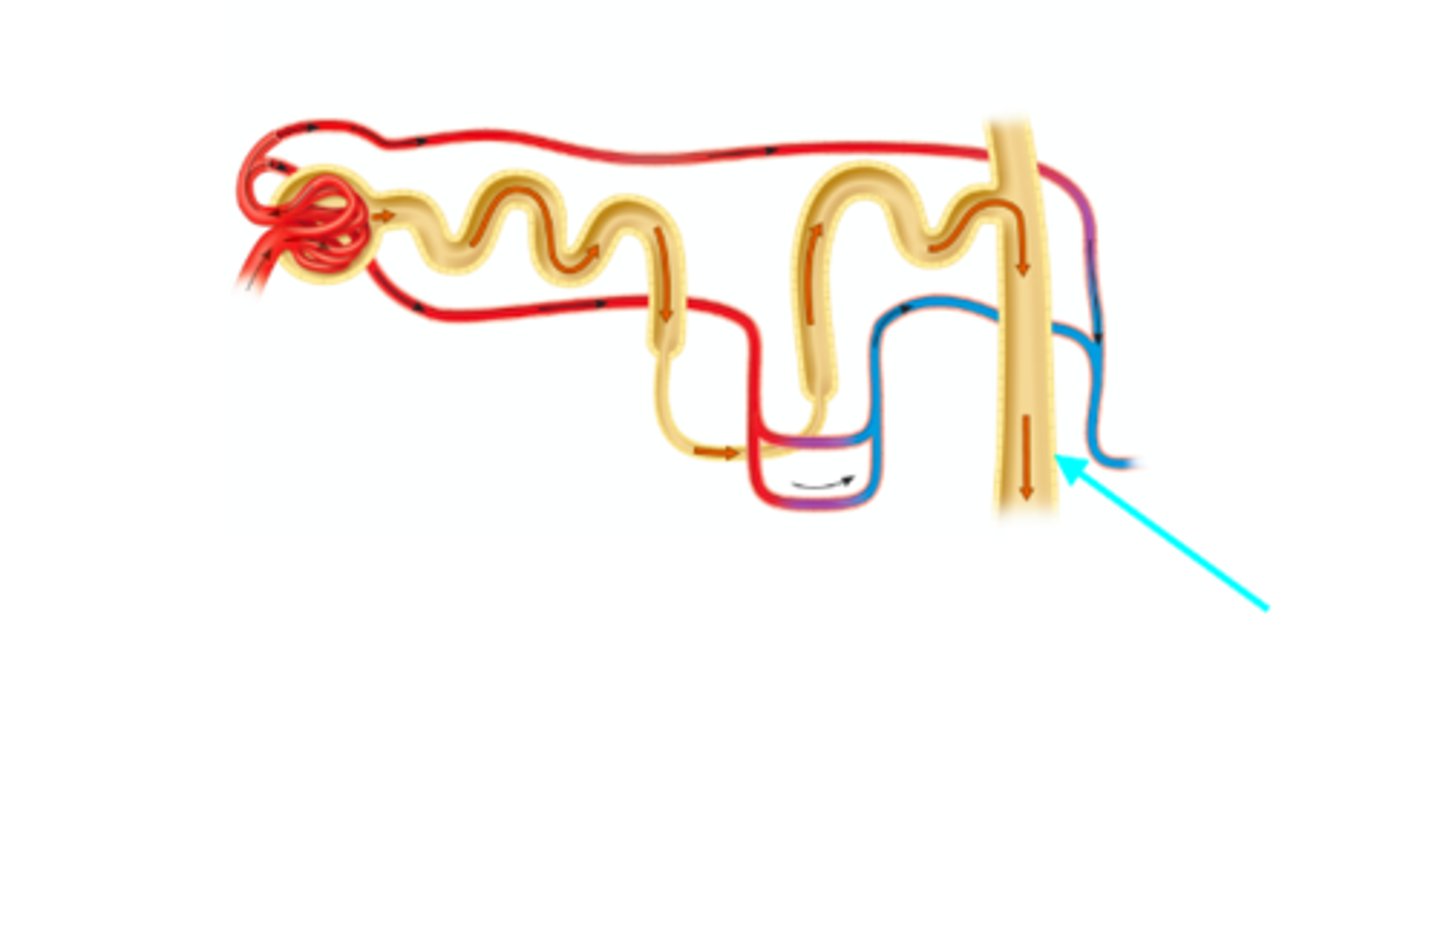

Cortical nephron

What structure of the kidneys is the blue arrow pointing at?

Juxtamedullary nephron

What structure of the kidneys is the blue arrow pointing at?

Collecting duct

What structure of the kidneys is the blue arrow pointing at?

Descending limb of the nephron loop

What structure of the kidneys is the blue arrow pointing at?

Ascending limb of the nephron loop

What structure of the kidneys is the blue arrow pointing at?

Nephron loop

What structure of the kidneys is the blue arrow pointing at?

Renal artery → Interlobar arteries → arcuate arteries → cortical radiate arteries → afferent arteriole → glomerular capillaries → glomerular capsule → proximal convoluted tubule → descending limb of nephron loop → ascending limb of nephron loop → distal convoluted tubule → collecting duct → minor calyx → major calyx → renal pelvis → ureter → urinary bladder → urethra

What is the pathway of a molecule as it travels from the renal artery to the urethra? Assume this molecule freely filters and is not reabsorbed.

Renal artery → Interlobar arteries → arcuate arteries → cortical radiate arteries → afferent arteriole → glomerular capillaries → efferent arteriole → peritubular capillaries → proximal convoluted tubule → descending limb of nephron loop → ascending limb of nephron loop → distal convoluted tubule → collecting duct → minor calyx → major calyx → renal pelvis → ureter → urinary bladder → urethra

What is the pathway of a molecule as it travels from the renal artery to the urethra. Assume this molecule does not filter and is actively secreted